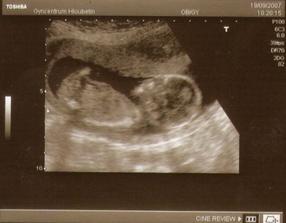

19.9.2007 - 3. ultrazvuk, miminko má už 15,8 cm 🙂, odběry na tripple test, váha 61 kg